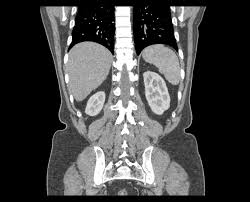

신장은 어떤 역할을 하는 장기일까

신장은 혈액 속 노폐물과 과도한 수분을 걸러 소변으로 배출하는 역할을 합니다. 이와 함께 혈압 조절, 체내 전해질 균형 유지, 적혈구 생성에 관여하는 호르몬 분비까지 담당합니다. 신장 기능이 떨어지면 부종, 피로, 혈압 이상처럼 다양한 신호가 서서히 나타날 수 있습니다.